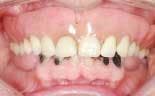

The patient is a 50-year-old male who is in good general health (figure 1). His chief complaint was the deterioration of his lower teeth (figure 2). He has been wearing a complete upper denture for about 20 years. His desire was to have fixed teeth in both the upper and lower arches.